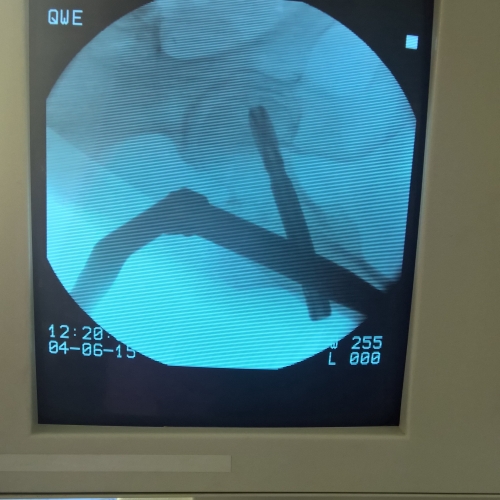

Современная методика лечения переломов бедренной кости - система PFNA (Proximal Femoral Nail Antirotation)